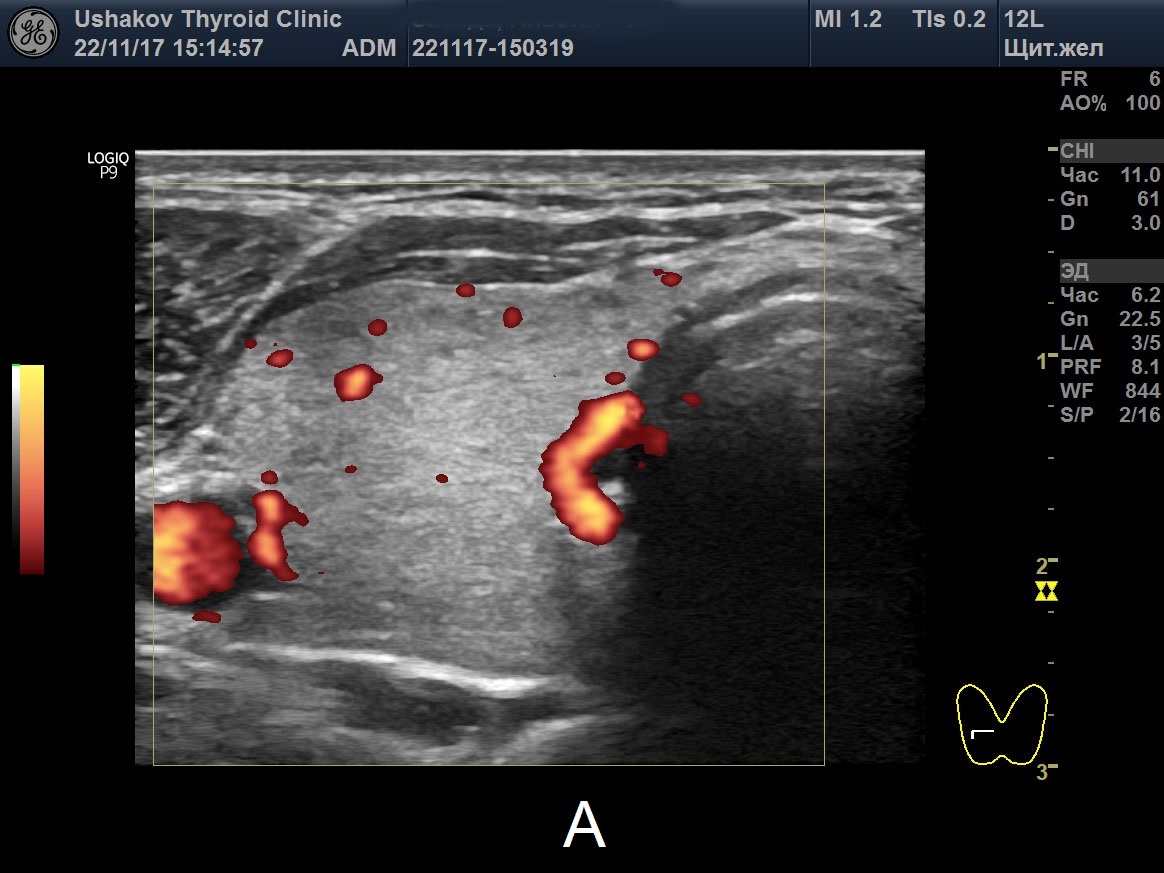

Цдк в узи щитовидной

Цдк в узи щитовидной 110 фото